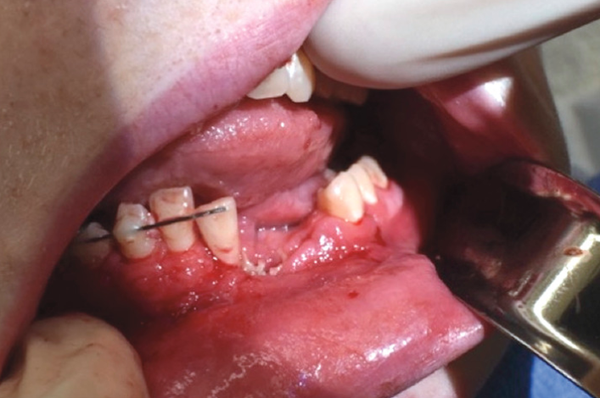

In addition to a fractured mandible, a chunk of the teen’s jaw was missing, and a hole was created through his chin, according to the article accompanying the graphic images.

“I’ve dealt with lots of facial trauma . . . and dealt with some really kind of exotic things like grizzly bear attacks and things like that, but this is one that I had never seen before,” Jonathan Skirko, the teen’s surgeon, told the Washington Post Thursday.